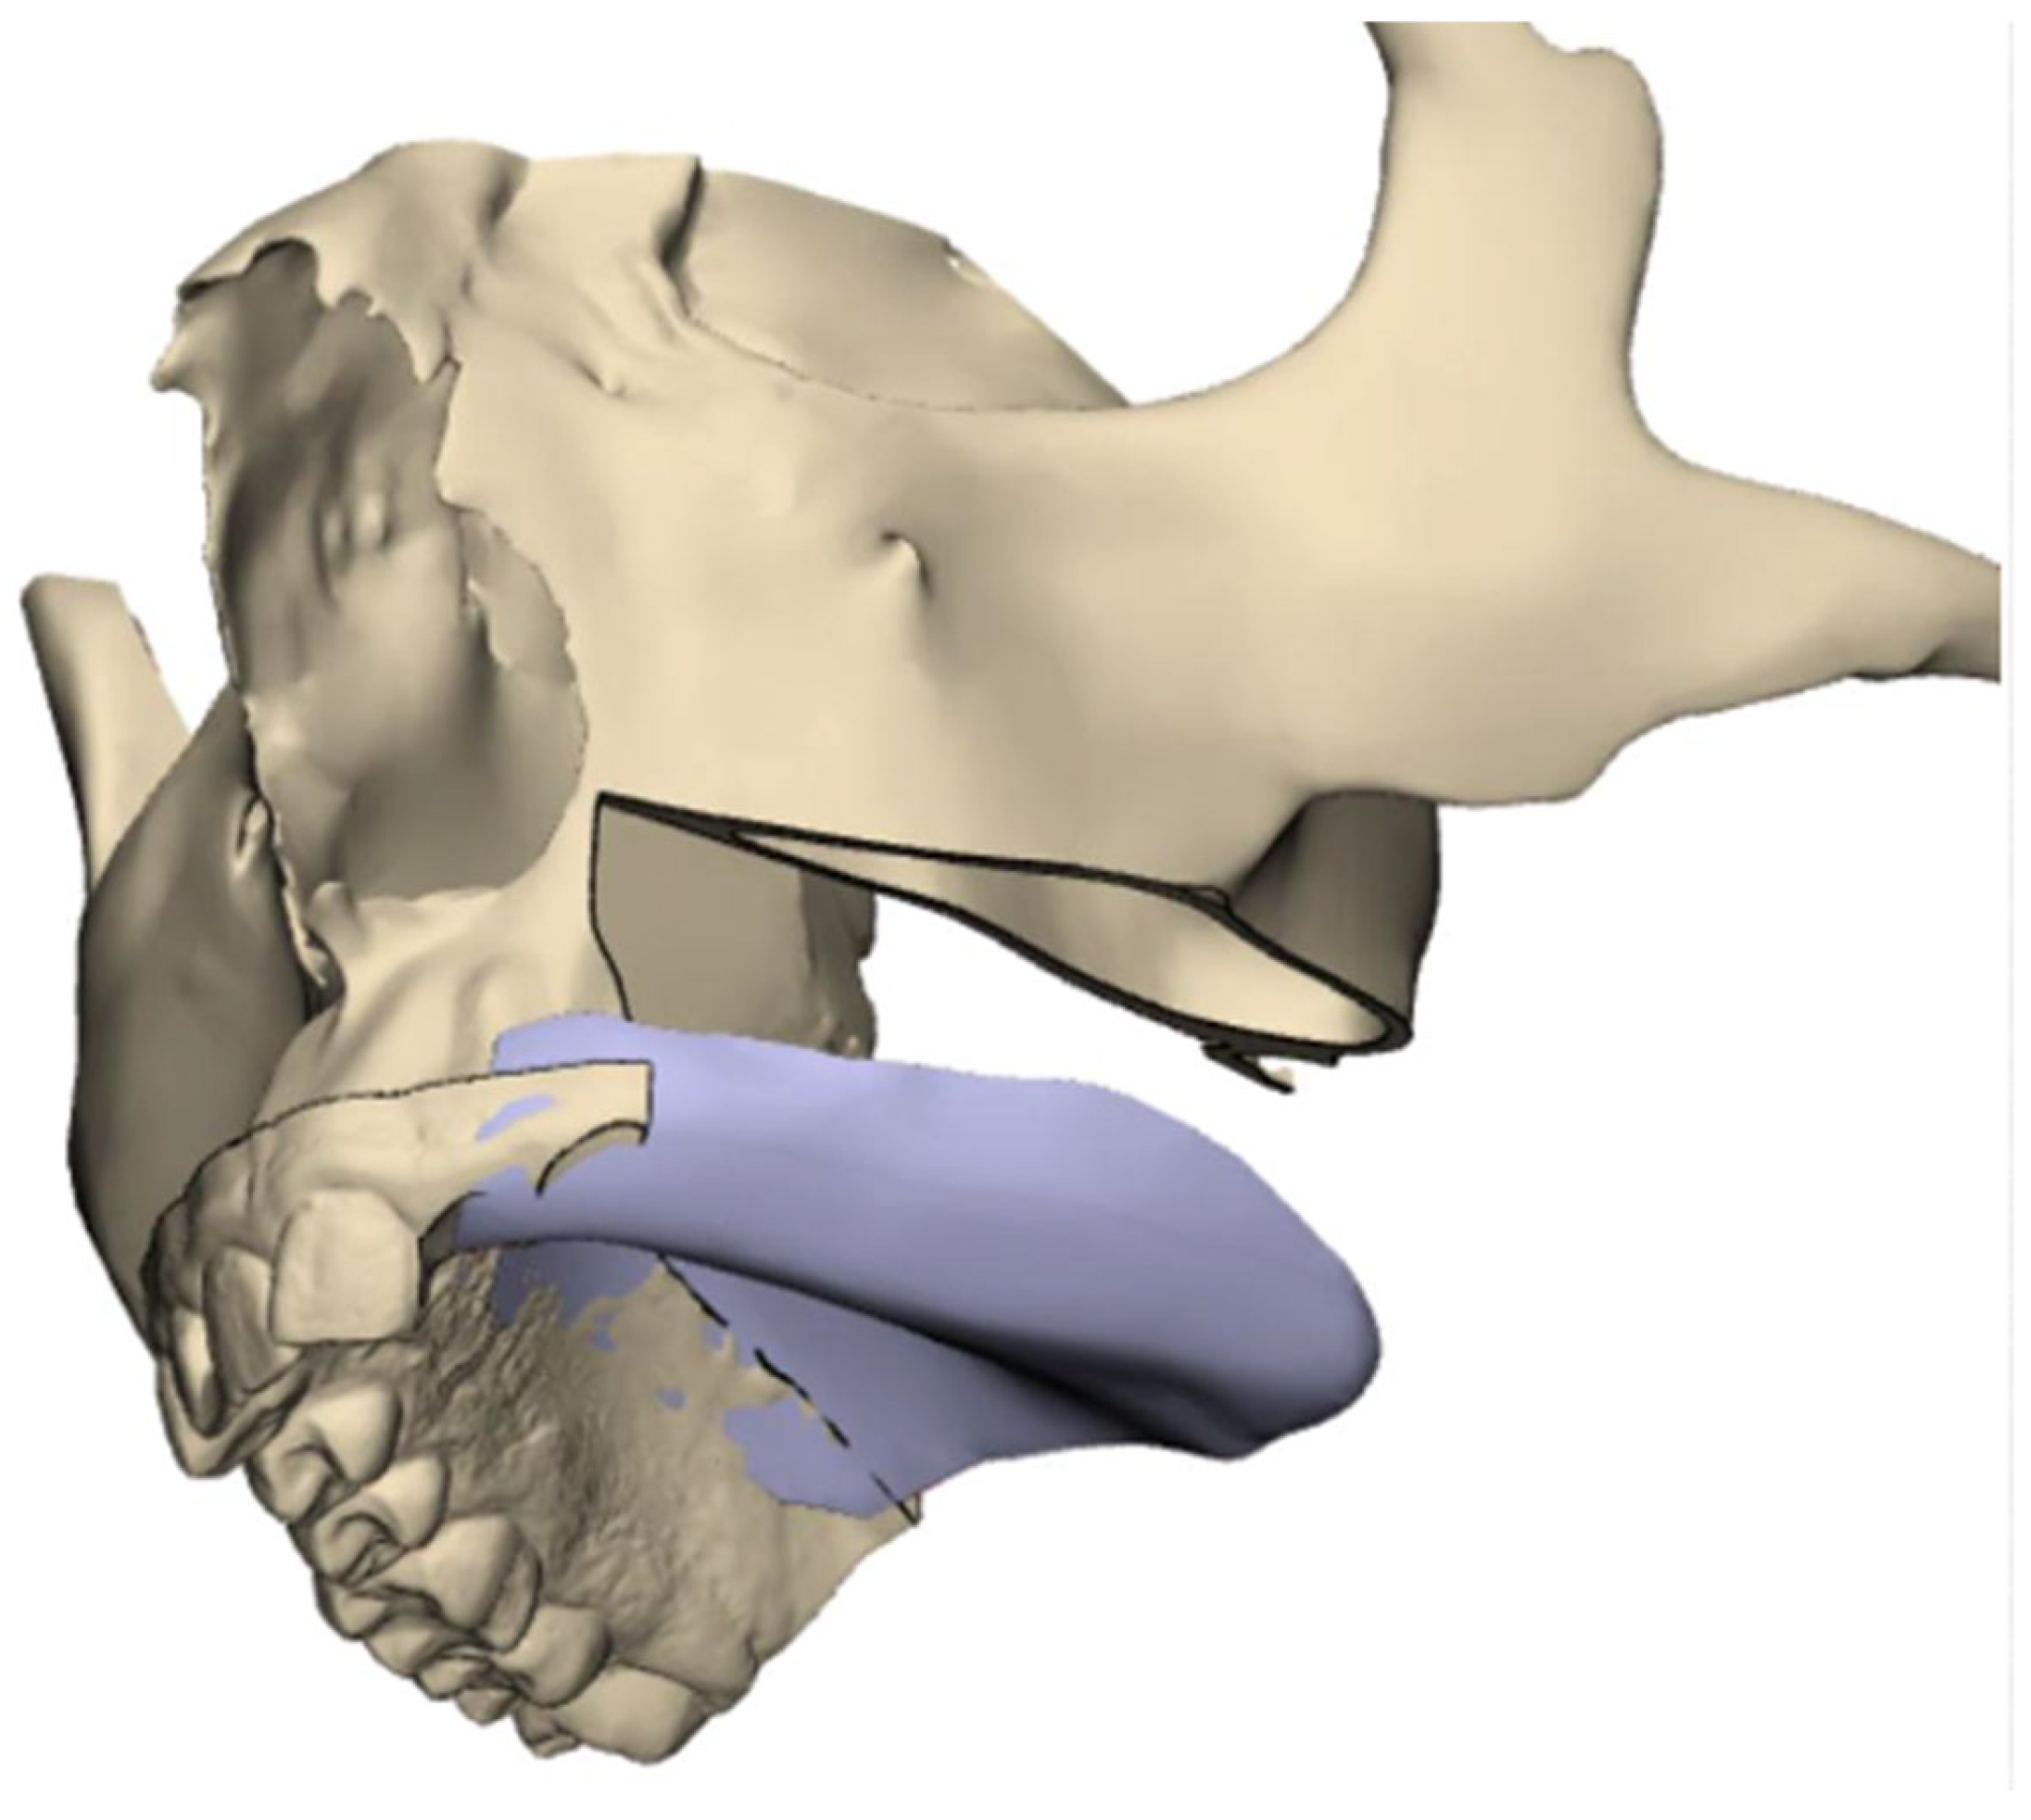

- Virtual resection: Execute virtual resection according to the tumor size and planned margins.

- Implant planning: Using a dental scan of both jaws, plan the positions of zygomatic implants and abutment emergence to fit the dental arch and occlusion. As a guideline, we aim for 15 mm vertical distance between the implant platform and opposing teeth.

- Surgical guide preparation: Plan a surgical guide for both zygomatic and standard implants (Figure 9). Ensure that the guide fits accurately to the post-resection maxillary and zygomatic defect boundaries. We recommend printing a 3D model to help the surgeon visualize the expected surgical defect (Figure 10). For cases with high uncertainty, surgical cutting guides can be printed (though they were not used in this case).